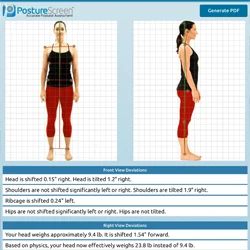

Computer Aided Posture Analysis

Computer-aided posture analysis testing is used to assess postural dysfunction and help formulate clinical assessments. It is an extremely helpful tool to demonstrate to our patients what kinds of issues they have and to address and to track progress.